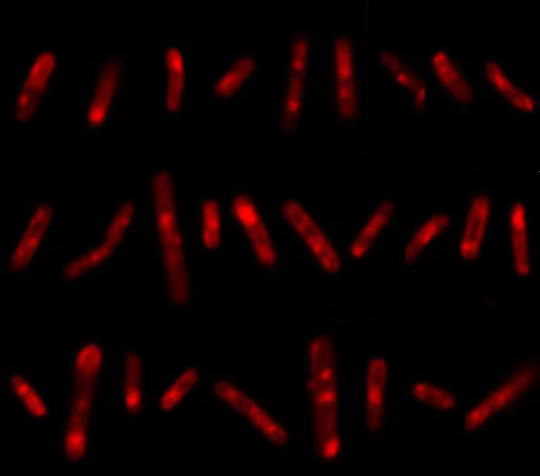

在华女士的诊断上,卢洪洲就应用了一种新型活菌代谢标记技术。该技术的核心是一种可以参与到结核分枝杆菌的生物合成过程中的荧光探针,可以实现对结核分枝杆菌快速、特异性标记。

周泱介绍:“这个探针能够特异性地‘咬’住结核分枝杆菌的糖蛋白,同时它还带有一条‘尾巴’,如果糖蛋白是活性的,就代表这个结核分枝杆菌是活的,探针的‘尾巴’就会亮起荧光,灵敏度非常高。”

通过这种检测方法,医护人员在华女士的血液和尿液标本里找到了大量活的结核分枝杆菌,结合肾脏功能指标,她被确诊为肾结核,接受了为期6个月的抗结核治疗。从治疗起,华女士的症状就逐渐消失,肾脏功能指标也在好转。

华女士的检测结果 亮起荧光代表有活的结核分枝杆菌